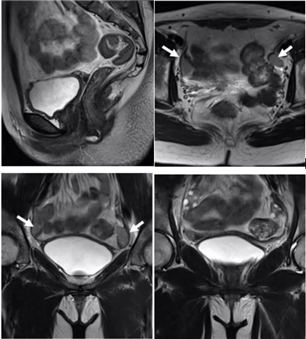

单角子宫

一侧副中肾管发育正常,另一侧副中肾管未发育或未形成管道(副中肾管下段发育不全则形成残角子宫)

伴或不伴残角,残角体积小,可存在内膜腔,可同外界相通

有宫内膜腔的残角,与单角子宫相通

有宫内膜腔的残角,不与单角子宫相通

残角内无内膜腔

无残角

子宫呈梭形或香蕉形,偏向盆腔一侧,T2WI解剖分层正常,无倒三角宫腔形态